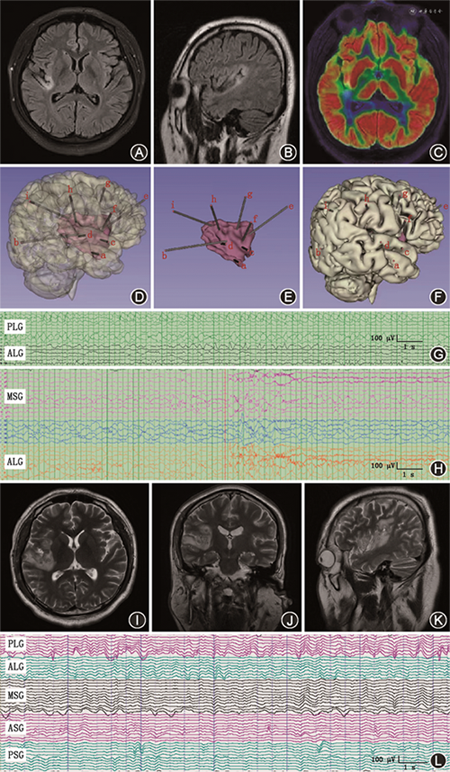

以2号患者为例,男性,31岁,发作表现为左侧肢体的麻木、活动障碍及吞咽动作,发作期间伴有左耳耳鸣。MRI可见右侧岛叶皮质脑回样异常信号,FLAIR上为高信号,PET-CT显示右侧岛叶部分代谢减低。行SEEG电极植入,斜行覆盖右侧岛叶前后部,垂直覆盖额叶岛盖,角回至岛叶,颞横回、中央区至岛叶等。发作早期脑电图显示第二岛长回内的电极触点提前1~3 s出现低幅快节律放电,并扩散至第一岛长回。颅内电刺激2 mA即可诱发惯常发作,考虑第一、二岛长回为致痫区域,对其进行重点毁损,对岛长回内垂直距离<7 mm的电极触点进行交叉毁损。术后复查MRI提示毁损后组织学改变与术前计划一致,患者至今保持癫痫完全缓解(图2)。